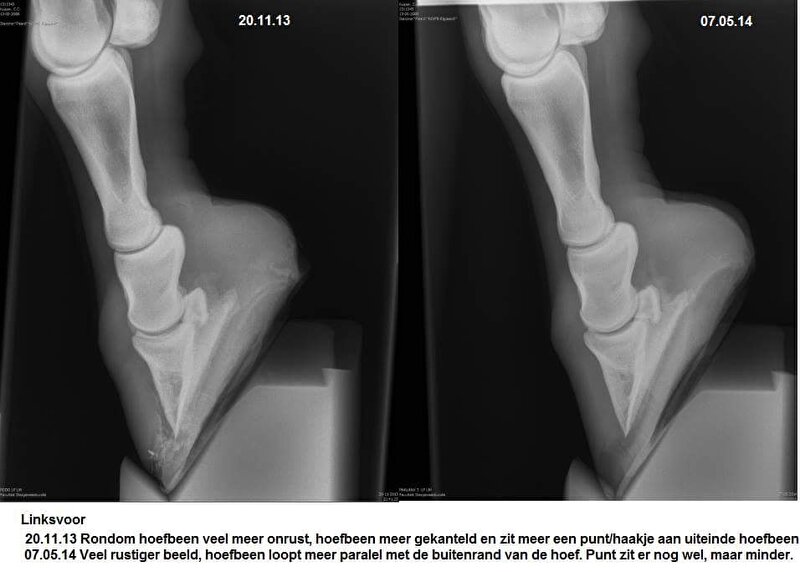

Hier nog wel wat foto's van haar herstel:

Cardy @ [BEH] White Line Disease.. al 12 weken uit de running. Ervaring?